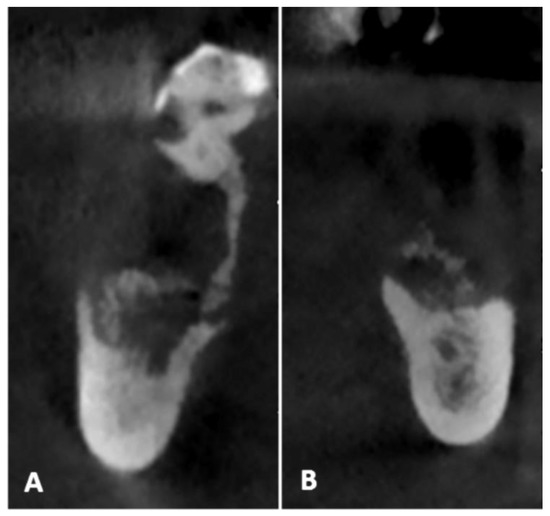

- Pre-operative evaluation. The patient undergoes a cone-beam CT exam with a reference plate containing the fiducial markers, fixed on his inferior teeth. The Digital Imaging and Communications in Medicine (DICOM) were imported into the navigation software.

- Surgery timing. The surgeon can follow in real time the ultrasonic tip position onto the system screen displaying the CBCT images and safely identify and remove the necrotic bone surrounding the inferior alveolar nerve on the right side.